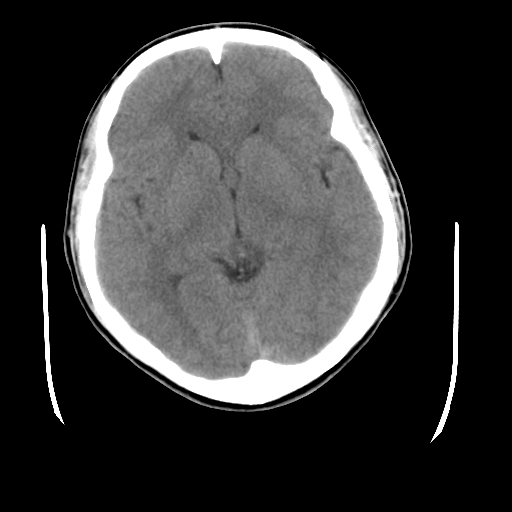

标题: CT23601:男, 17岁,剧烈头痛一小时。 [打印本页]

标题: CT23601:男, 17岁,剧烈头痛一小时。

男, 17岁,剧烈头痛一小时。

颅脑ct平扫颅内未见明确异常;剧烈头痛,建议必要时dsa造影。